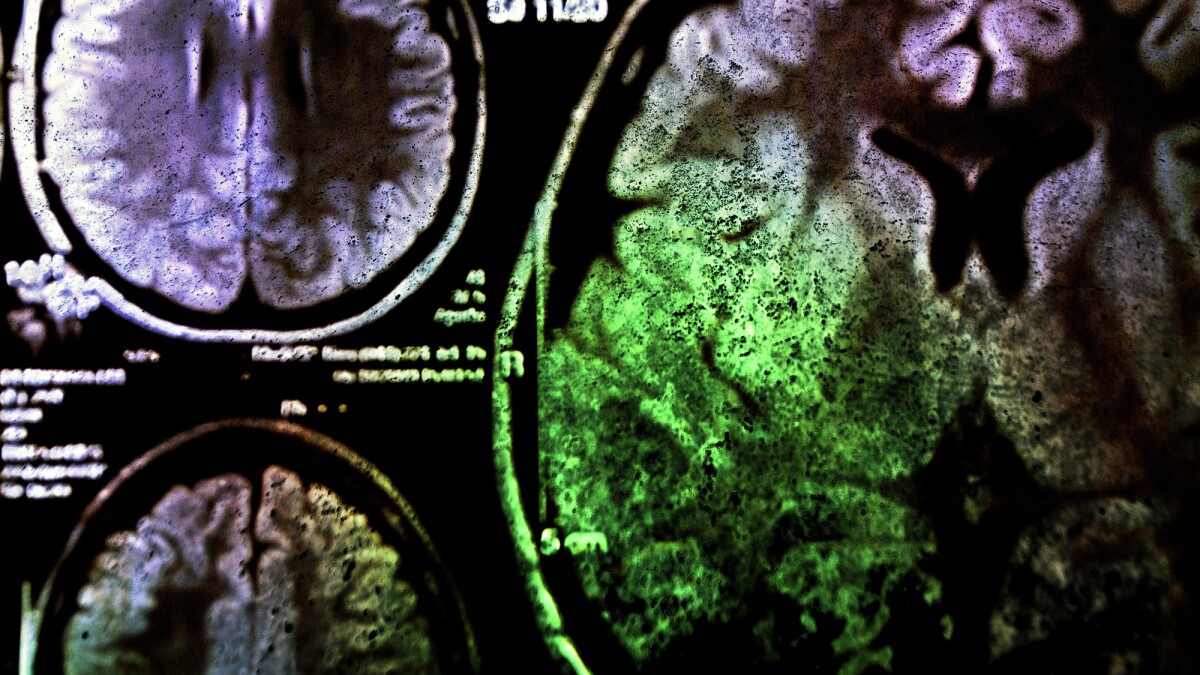

New approach shields memory from brain cancer radiotherapy

by Paul McClure

A new study offers hope for brain cancer patients facing memory loss from radiotherapy. By blocking a single immune receptor, scientists preserved cognition in mice without dulling the cancer-killing power of radiation.